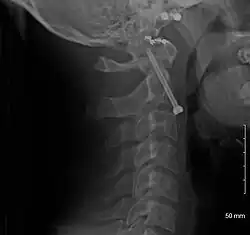

A fracture of both pedicles of the axis is termed a Hangman's fracture.

Fractures of the dens are classified into three categories according to the Anderson Alonso system:

- Type I fracture - Extends through the tip of the dens. This type is usually stable.

- Type II fracture - Extends through the base of the dens. It is the most commonly encountered fracture for this region of the axis. This type is unstable and has a high rate of non-union.

- Type III fracture - Extends through the vertebral body of the axis. This type can be stable or unstable and may require surgery.[1]

-

A fracture of the base of the dens as seen on plain X-ray -

A fracture of the base of the dens as seen on CT -

Type 3 odontoid fracture -

Type 2 dens fracture